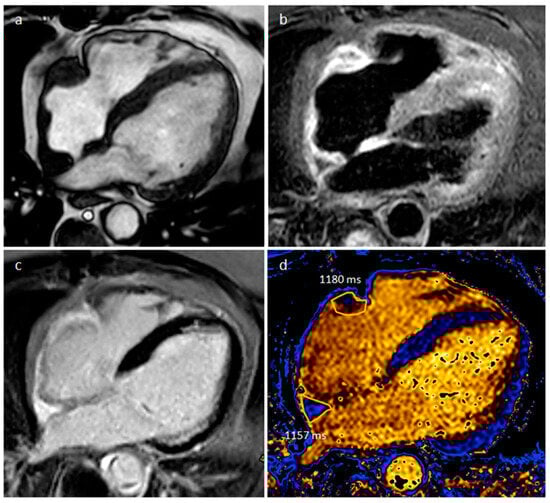

- Nasser, S.B.; Doeblin, P.; Doltra, A.; Schnackenburg, B.; Wassilew, K.; Berger, A.; Gebker, R.; Bigvava, T.; Hennig, F.; Pieske, B.; et al. Cardiac Myxomas Show Elevated Native T1, T2 Relaxation Time and ECV on Parametric CMR. Front. Cardiovasc. Med. 2020, 7, 602137. [Google Scholar] [CrossRef]

| Myxoma | Adulthood. Carney complex. | LA | Usually, asymptomatic. Rarely, intracardiac obstruction, embolic events and constitutional symptoms | Mobile mass arising from the IAS | Globular or spherical, with a friable surface and heterogeneous internal echogenicity | Heterogeneous, low attenuation, may be calcified | Isointense T1w, High T2w, heterogeneous LGE |